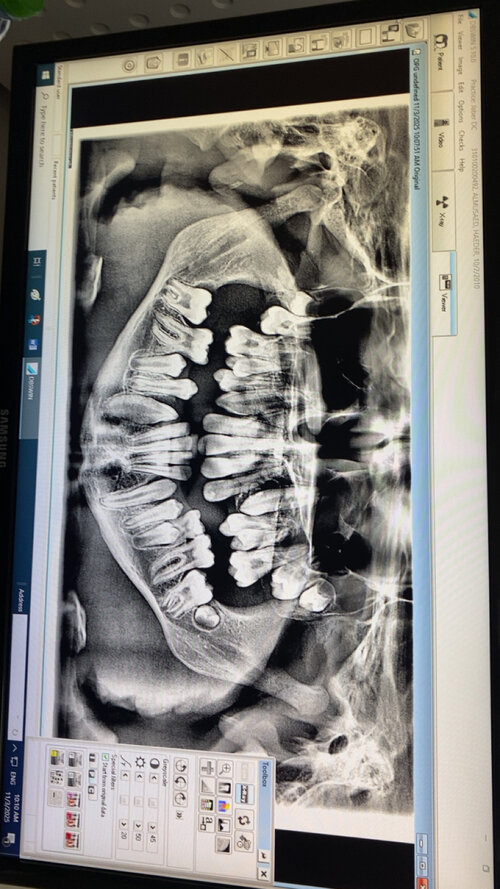

I’m getting a RME on Wednesday recommend by my orthodontist do I need it or will it fuck me up? I heard for some people it went really well and for some it ruined them.